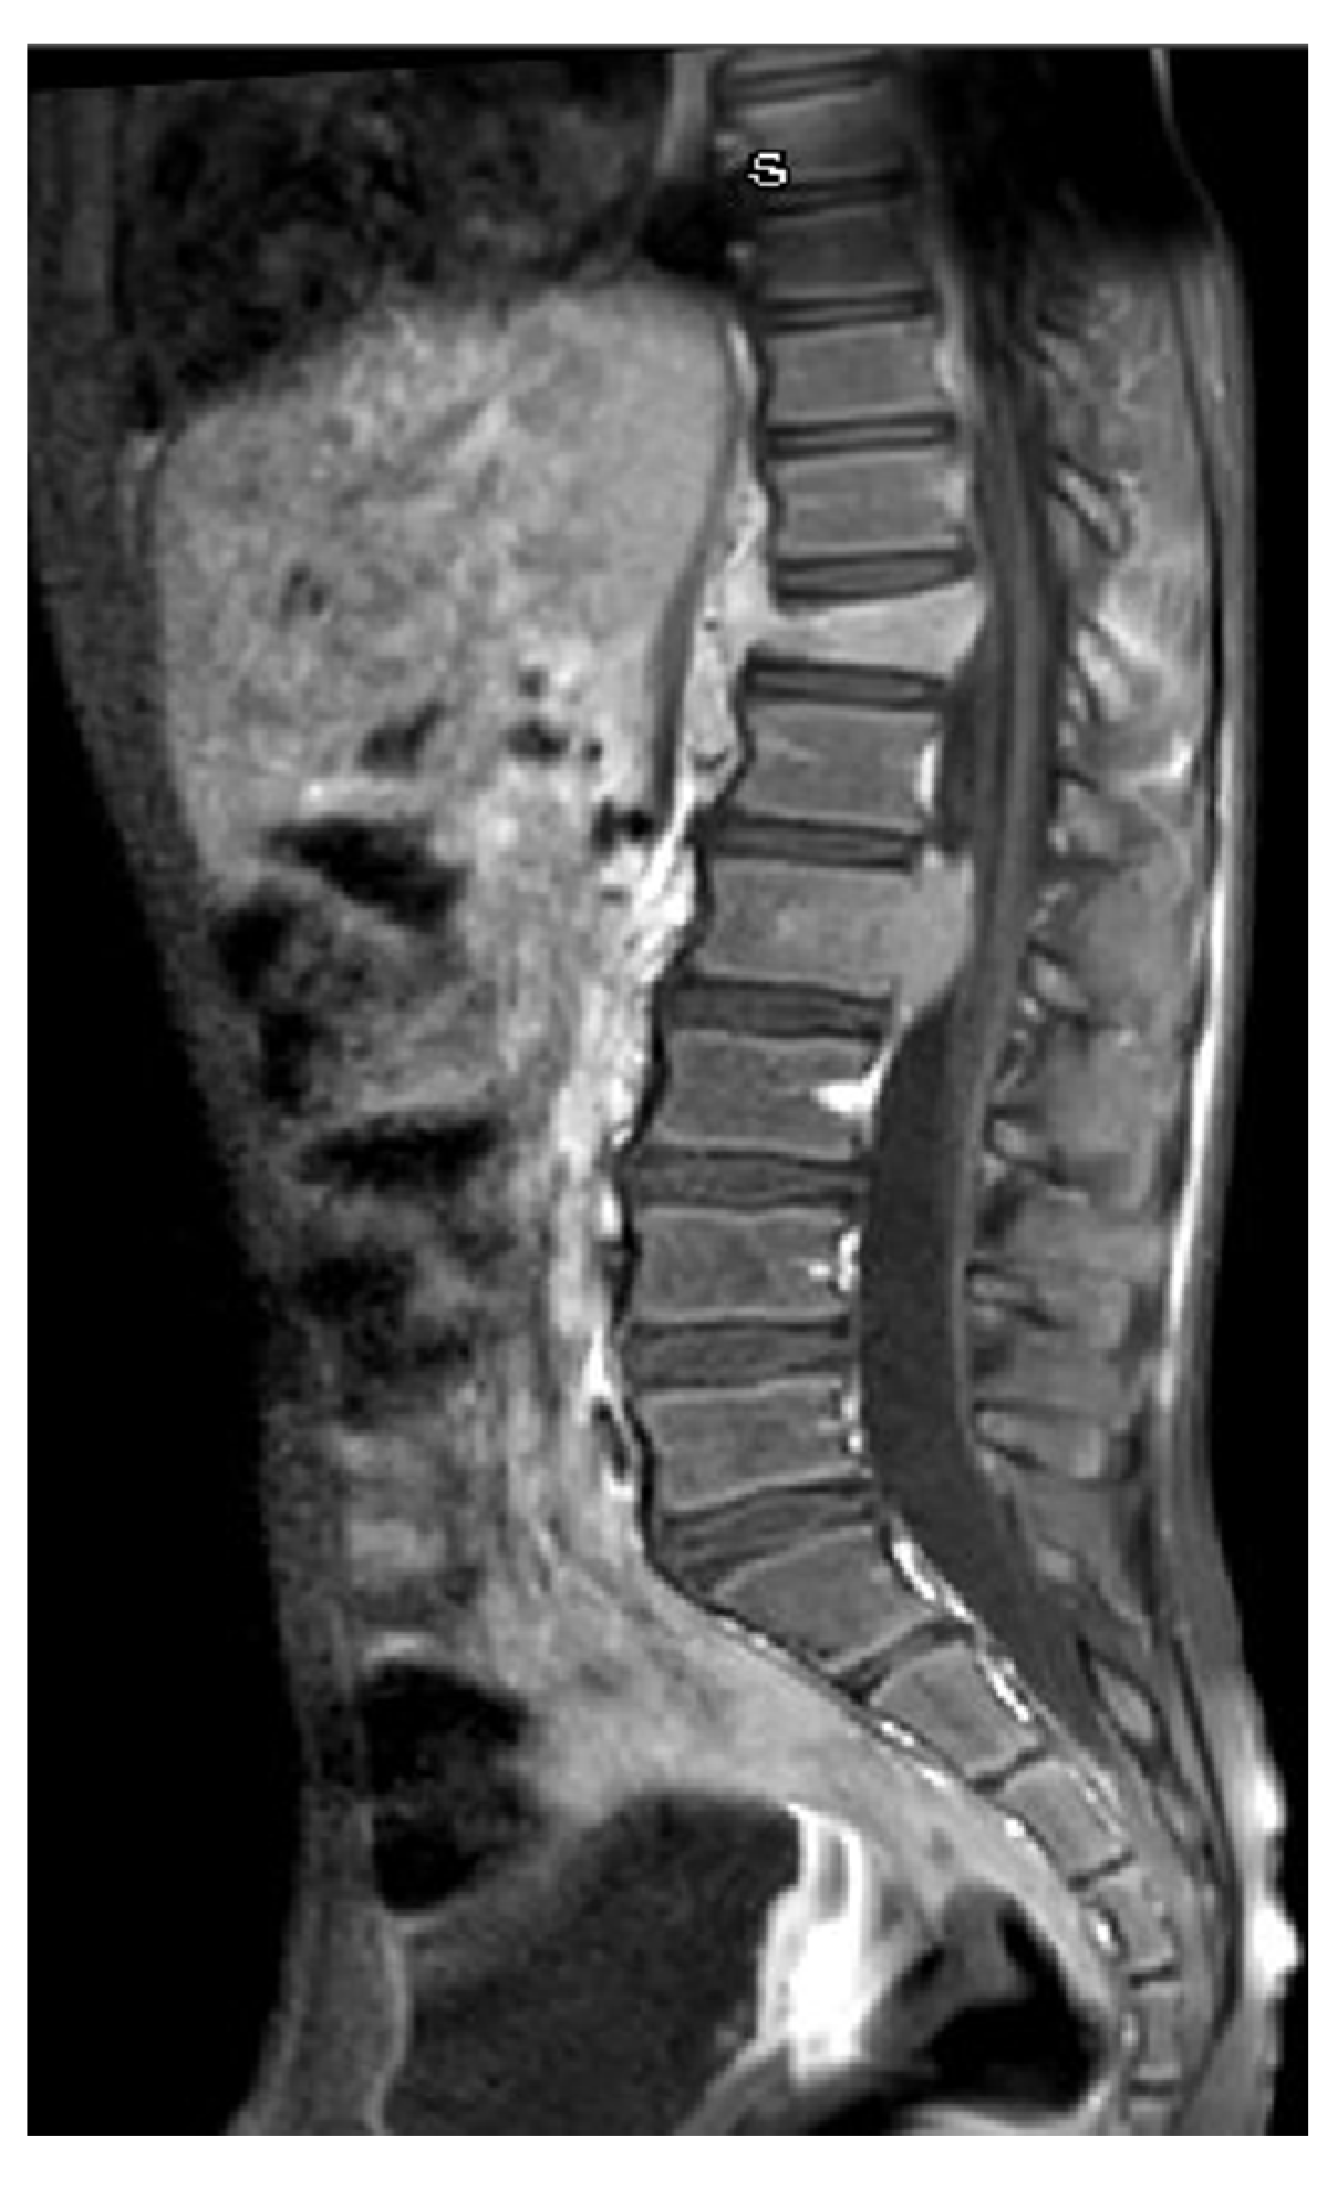

A previously healthy 9-year-old boy came to our attention for back pain, lasting more than 2 months, with no other symptoms; he had been treated with physiotherapy and anti-inflammatory drugs. On clinical examination, the boy was well-appearing, complaining of moderate back pain at the lumbar level. Complete blood count, lactate dehydrogenase, uric acid, C-reactive protein, and erythrocyte sedimentation rate were in the normal range. Spine magnetic resonance imaging (MRI) showed a signal alteration at the D12-L2 level (with a wedge-shaped D12 body) characterized by hypointensity at T1-weighted and hyperintensity at T2-weighted sequences; furthermore, an abnormal tissue involving medullary canal and neural foramina was appreciated at the D11-L1 level (Figure 1). Cerebral, thorax, and abdominal CT were of normal appearance. The boy underwent an open biopsy, and the histological diagnosis was ALCL, CD30+, ALK+, EMA+, perforin+, associated with numerous histiocytes CD68PGM1+. Positron emission tomography/computed tomography (PET-CT) showed high fluorodeoxyglucose (FDG) uptake at D11-L2 level, with spinal cord involvement. Lumbar puncture revealed the presence of 66 T-lymphoblasts/μL in the cerebrospinal fluid (CSF) and bone marrow aspirate was positive for NPM-ALK transcript, detected by qualitative RT-PCR. The patient was treated with six courses of chemotherapy according to the AIEOP LNH-97 protocol for ALCL, high-risk group, with CNS involvement (Table 1) [3]. MRD in bone marrow and peripheral blood was negative just after the first course of chemotherapy. PET-CT, performed after the second chemotherapy block, showed a complete metabolic response, confirmed also at the end of treatment. Spine MRI performed 2 weeks after stop-therapy demonstrated complete disappearance of both D12-L1 lesions and tissue proliferation in the D11-L1 region, with the persistence of mild signal alteration, without any contrast enhancement, at the L2 level only (Figure 2). During the follow-up, the boy was also monitored by the analysis of MRD in peripheral blood every month for the first three months, then every two months up to one year from the stop-therapy: NPM-ALK transcript was never detected. The patient is in clinical, radiological, and molecular remission at 12 months after the end of treatment.

Figure 1. Spine MRI at onset: wedge-shaped D12 vertebral body and abnormal tissue proliferation with involvement of medullary canal at L1-L2 level.